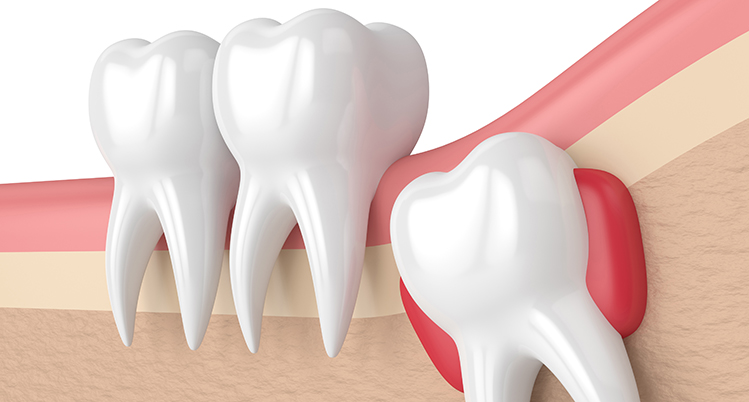

半分頭が出ている親知らずのイラスト

生え方により痛みは変わってきます。歯ぐきを裂きながら生えてくるため歯ぐきから歯の頭が出ようとするときは、歯が出るまでお痛みが続きますが、生えてしまえばお痛みは出ません。横や斜めに生えてくると手前の歯を押すためその痛みが続きます。

生えてくる際の痛みについて